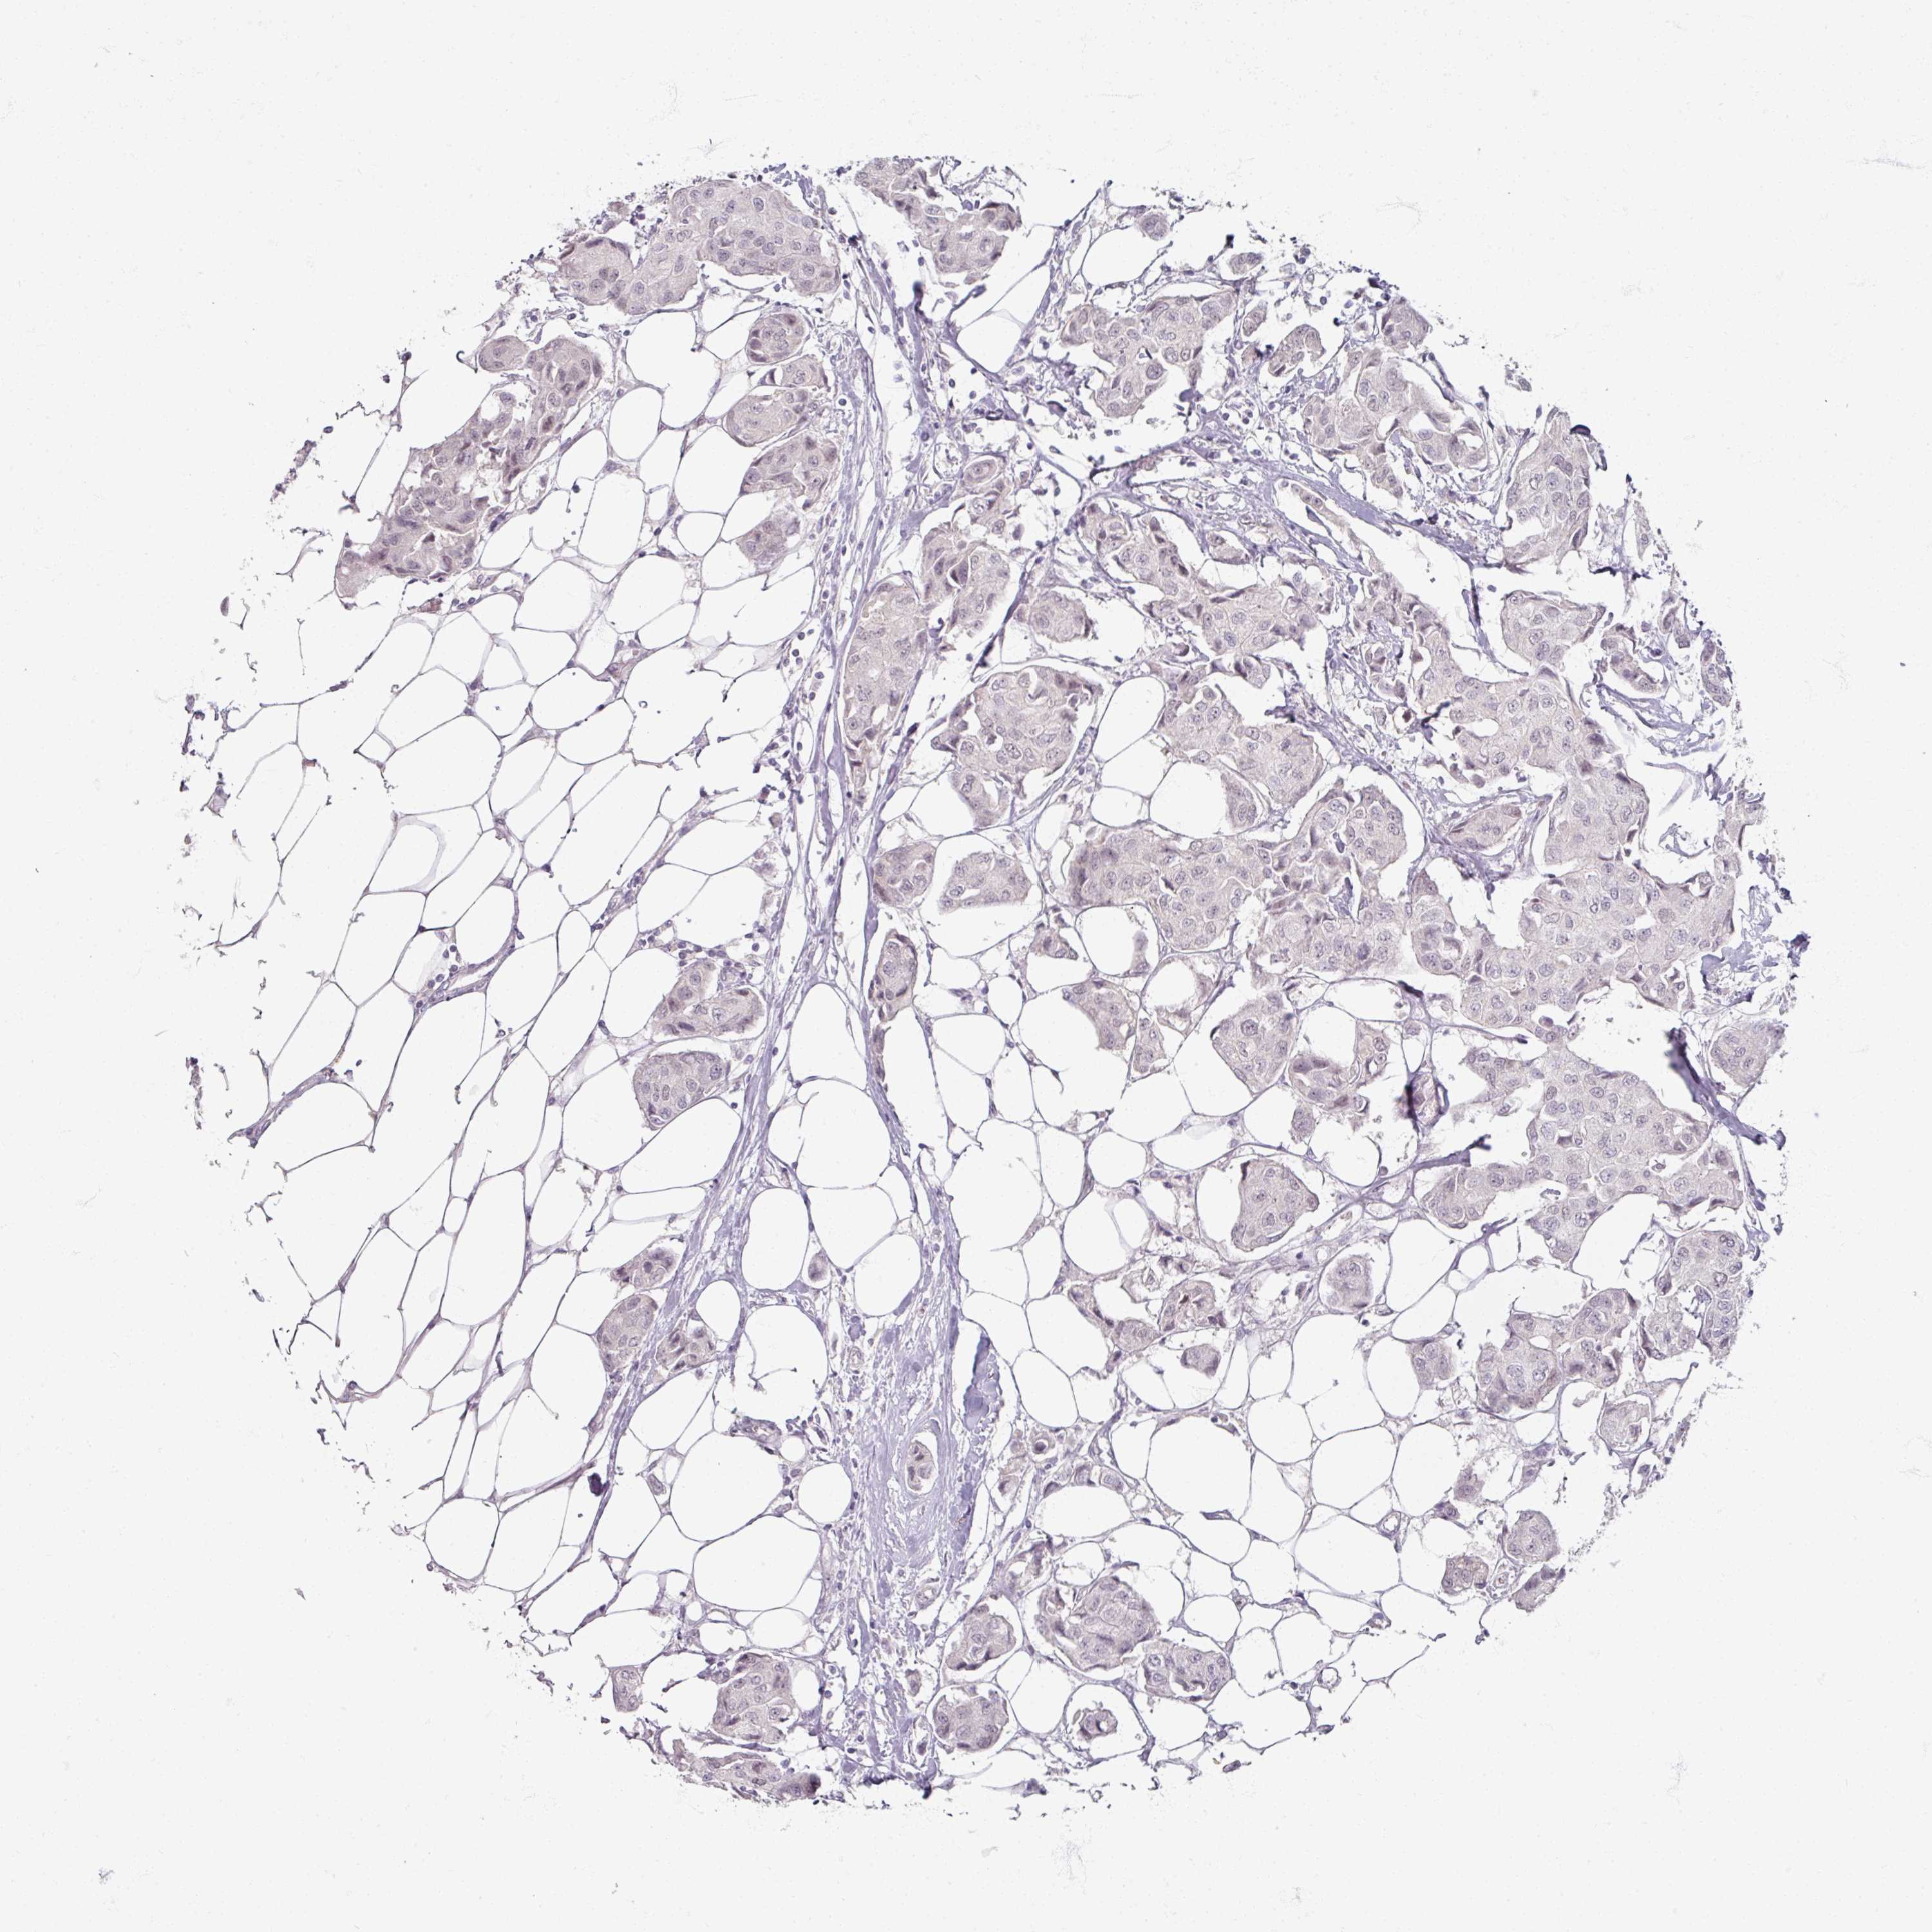

CANCER BREAST CANCER Show tissue menu

Breast cancer

Human cancer